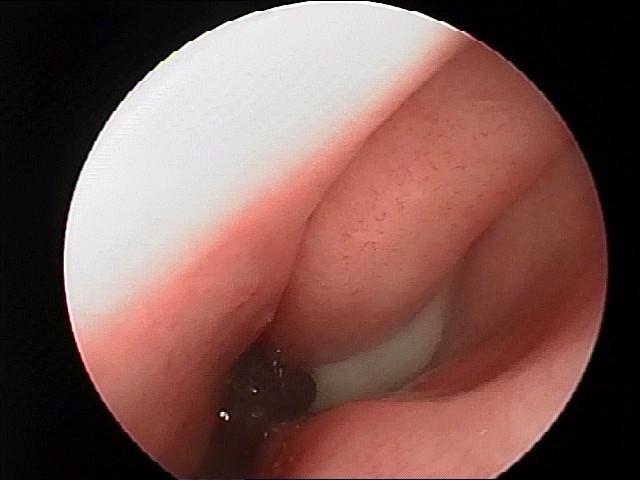

3、手术治疗:①鼻窦内窥镜手术,即利用光导纤维成像,有直观清晰、准确、导光率高的特点,配合专门的手术器械,明显提高手术的精确度,损伤小、针对性强,病变去除彻底,并发症少,预后好,复发率明显降低。鼻窦内窥镜手术需住院治疗。②辅助手术,为了达到鼻内镜鼻窦手术的效果,就需在清除病变的同时针对不同的病人做一些辅助手术,其中包括切除解剖变的中鼻甲,摘除中鼻道的息肉,咬除膨大的筛泡,纠正高位鼻中隔偏曲,部分下鼻甲切除等。这些手术看似与鼻窦手术无关,但可直接影响手术疗效,患者应对此有正确的认识,不要认为是医生额外增加的手术。